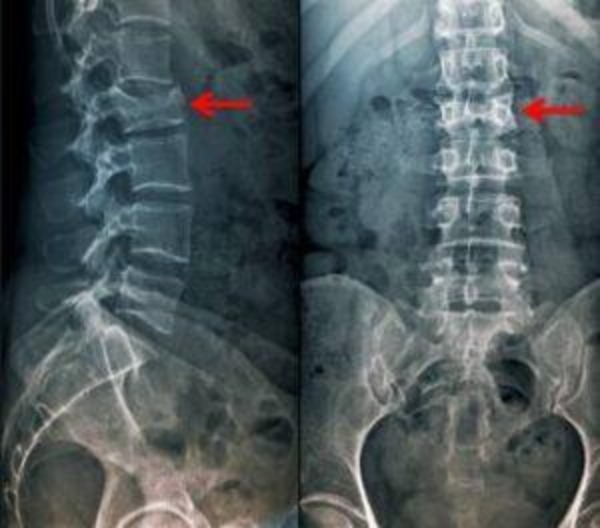

- تصویربرداری ساده با اشعه ایکس (رادیوگرافی): نخستین ابزار تصویربرداری برای تشخیص شکستگی مهرهها، عکس رادیولوژی ساده از ستون فقرات کمری است. رادیوگرافی میتواند شکستگیهای واضح استخوانی یا دررفتگی مهرهها را نشان دهد. معمولاً از نمای روبرو و نیمرخ کمر عکسبرداری میشود. هرچند در شکستگیهای ظریف یا برخی نواحی مهره ممکن است اشعه ایکس کافی نباشد، اما در دسترسترین روش اولیه محسوب میشود.